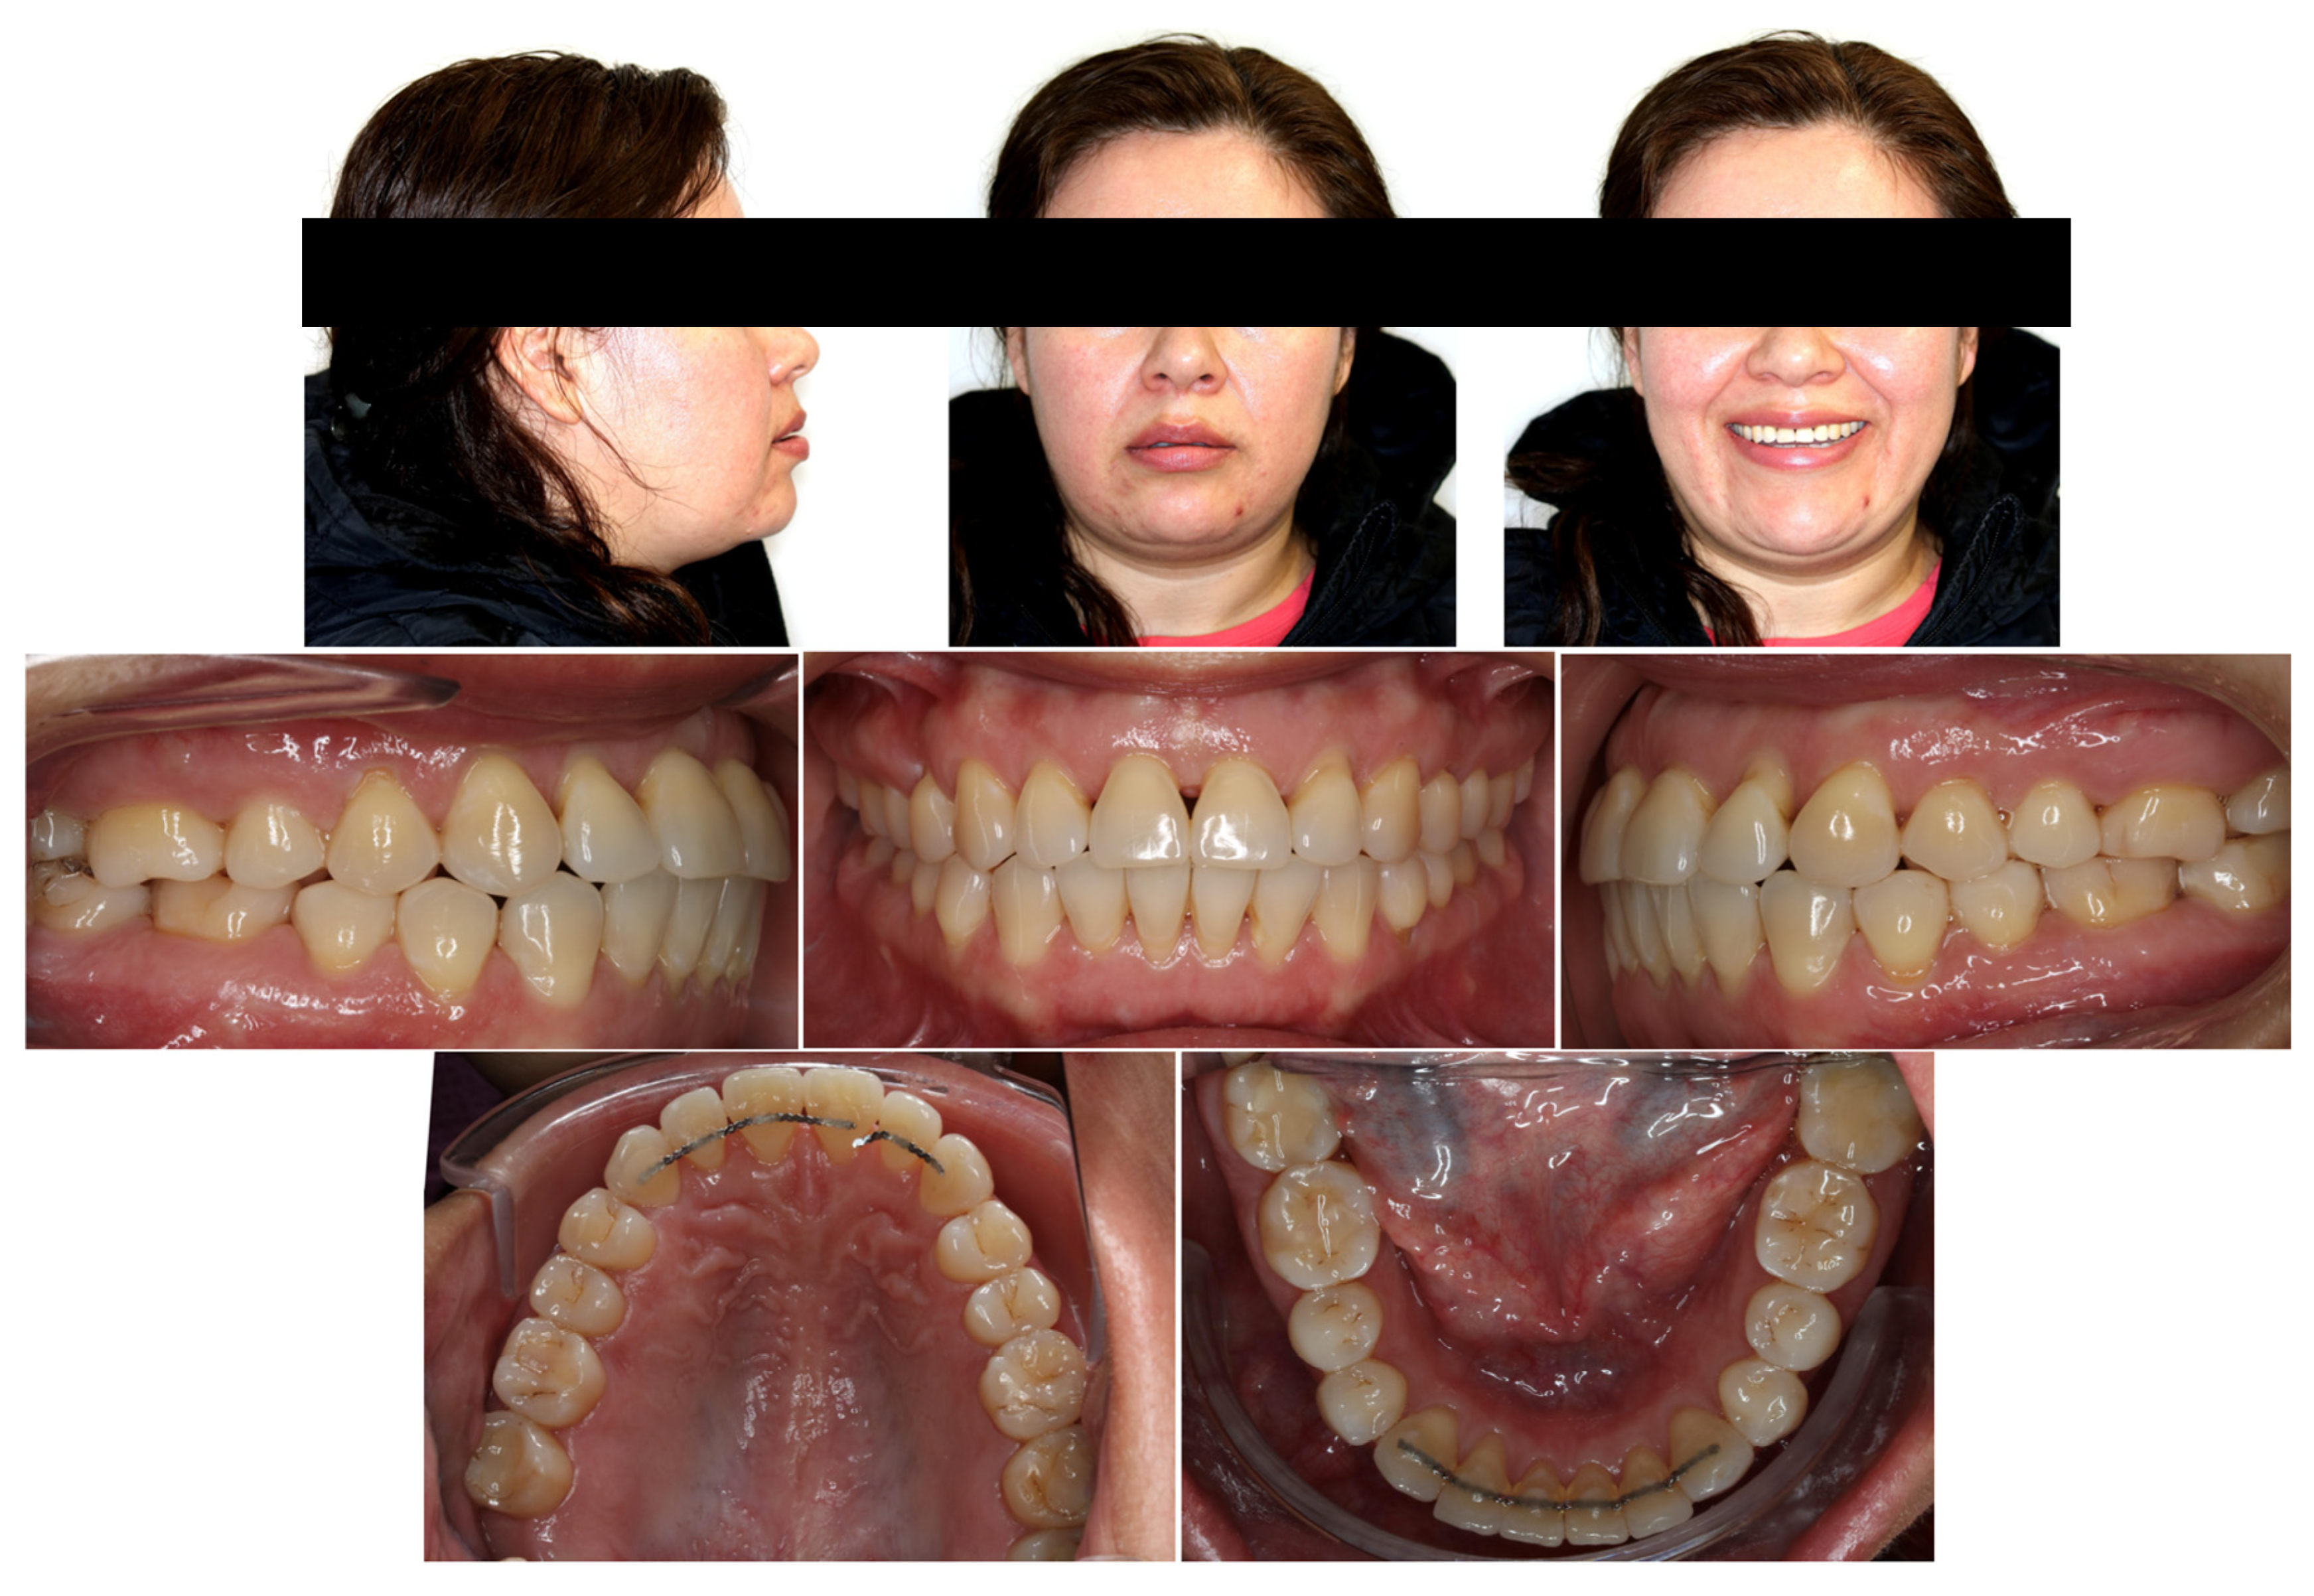

2. Case Presentation

3. Treatment Results